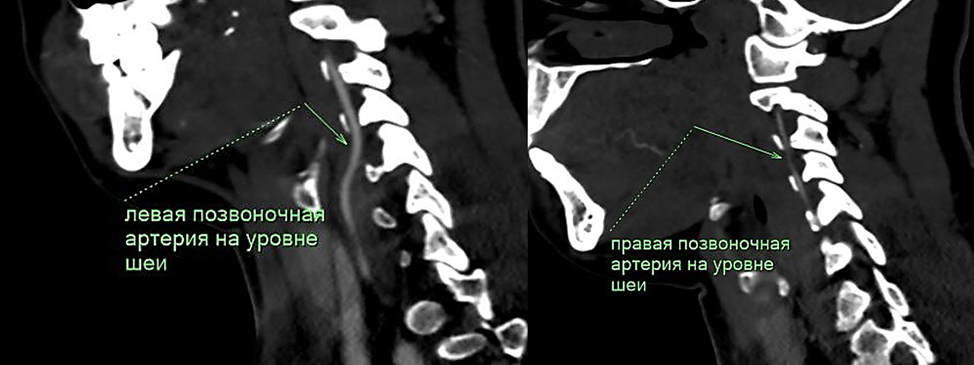

Рис. 1. Диаметр экстракраниальных отделов позвоночных артерий асимметричен D<S, справа нитевидная до 1 мм, слева 2,3 мм. Ход их ровный, равномерно заполнены контрастным веществом.